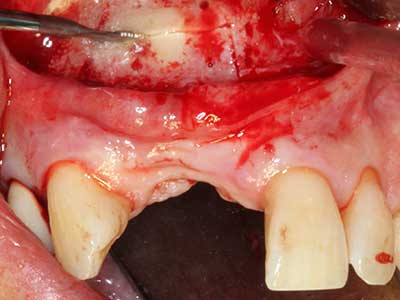

En la extracción de bloques óseos la piezocirugía también presenta ventajas adicionales: Además de la alta precisión en la osteotomía que ya se ha descrito antes, se ha comprobado que el uso de los delgados insertos de sierra resulta especialmente cuidadosas con el hueso. Frente a esto, sobre todo cuando se usan las fresas de Lindemann, cabe esperar pérdidas en la extracción significativamente más altas debido al mayor grosor de la parte frontal del cabezal (Lakshmiganthan, Gokulanathan et al. 2012). La separación basal que se necesita en particular en los injertos de bloque extraídos de forma retromolar se ve facilitada mediante sierras perpendiculares especialmente previstas a tal fin, lo que permite considerar que la cirugía piezoeléctrica es un procedimiento preciso y seguro para la obtención de bloques de hueso en el área retromolar (Happe 2007) (fig. 1-12).

Aplicación: Partición ósea / Cortical Split